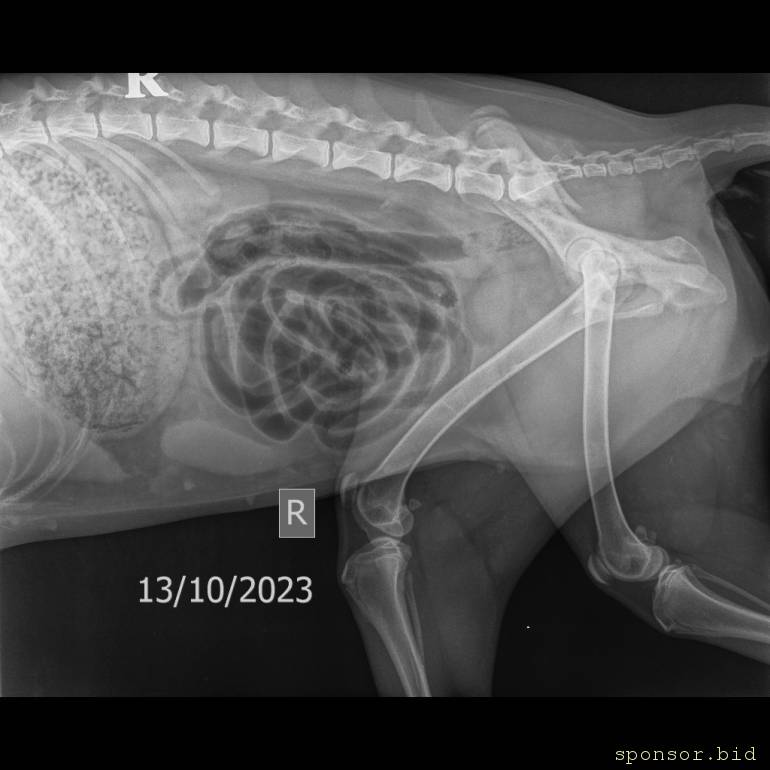

На втором снимке видно как раздроблена кость

Мою собаку сбила машина - Мягкие ткани Средний 10-25 kg -Брюшная полость LAT-13.10.2023-15_31_40-951.JPEG

Мою собаку сбила машина - Скелет средний 10-25 kg-Тазовые кости VD-13.10.2023-15_31_39-169.JPEG

Мою собаку сбила машина - Скелет средний 10-25 kg-Грудной-поясн. отд. LAT-13.10.2023-15_31_37-450.JPEG

Вчера вечером мою собаку паровой ХАСКИ ПО КЛИЧКЕ АСКА сбили у нее перелома тазабедреной кости и как мне ветеринар обьяснил под тазом есть ещё одна кость которая отвечает за то чтоб она могла наступать на лапы в итоге эта кость раздроблена он сказал в нашем городе нету технологий чтоб ей собрать ее нужно ехать в Самару я сам из Уральска

Операция стоит 15000 рублей пластина стоит 7000 анестезия 3000 р помимо этого перевозка собаки

Сказали операцию нужно сделать в течение 3-5 дней пока кость не начала обрастать

Если не сделать собака не сможет наступать на задние лапы а если будет она будет ими давить на органы